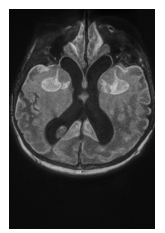

A 7-month-old Infant came to our hospital with her parent complaining that their child is not looking at objects, and her birth history revealed she was delivered at 34 weeks with a lower segment caesarean section (LSCS), her birth weight was 2.4 kg, and she cried immediately after birth. She was advised to undergo an MRI, which revealed normal (Figure 2). We examined her, and her anterior segment was within normal limits; no significant refractive error was found under cycloplegic examination performed with 1% cyclopentolate. However, her posterior segment examination revealed diffuse disc pallor in both eyes. Her visual acuity at the first presentation was unable to fix and follow objects, and she did not respond to the Lea paddle and Teller acuity card. Therefore, she was referred to a vision therapy clinic for further intervention. After one month of daily thirty-minute vision therapy for six weeks, the child's vision improved to 20/84, and they began to maintain eye contact and reach for objects (Figure 3). According to the clinical features of CVI, we have diagnosed this case as CVI, despite no abnormalities being found on MRI. Again, for this child, the pre-therapy Nutech score was 1, and after therapy, it increased to 5. We followed up on the case for up to six months with no other intervention, as she achieved her visual milestone, and no further deterioration was noted. Her final visual acuity was 20/41, and she was responding to the 1.25% Hiding Heidi chart and maintaining eye contact, with gross reaching being appropriate.

Figure 2 Undergone of MRI, which revealed normal.